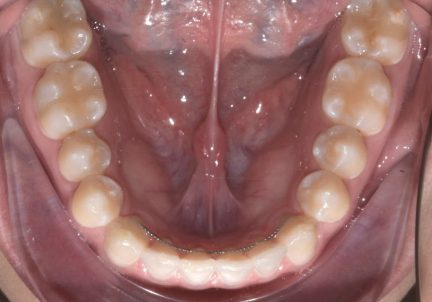

Mésialisation, nivellement de la courbe de Spee, ingression, expansion, rétraction, réduction interproximale, fermeture d'espace

- En raison d'un écart de Bolton, la réduction interproximale était nécessaire dans l'arcade inférieure pour obtenir une relation correcte entre le surplomb et le surplomb. La réduction interproximale établie entre l'incisive centrale supérieure n'a pas été appliqué, de sorte que la fermeture du diastème pouvait avoir un raccord avec les derniers aligners.